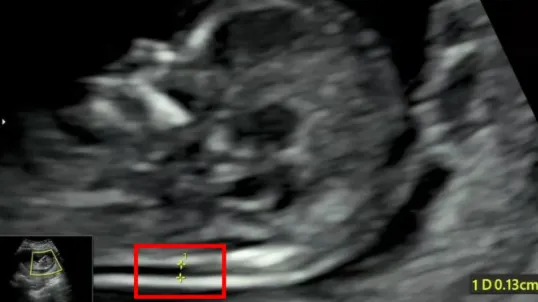

检查选在孕11~13周+6天进行,相当于头臀长45-84mm时测量,超过84mm检查结果会不准确。

NT增厚越明显,胎儿异常机会就越高,异常程度也会越严重。一般正常的NT厚度不能大于3mm,超过3mm表示NT增厚,存在异常可能。